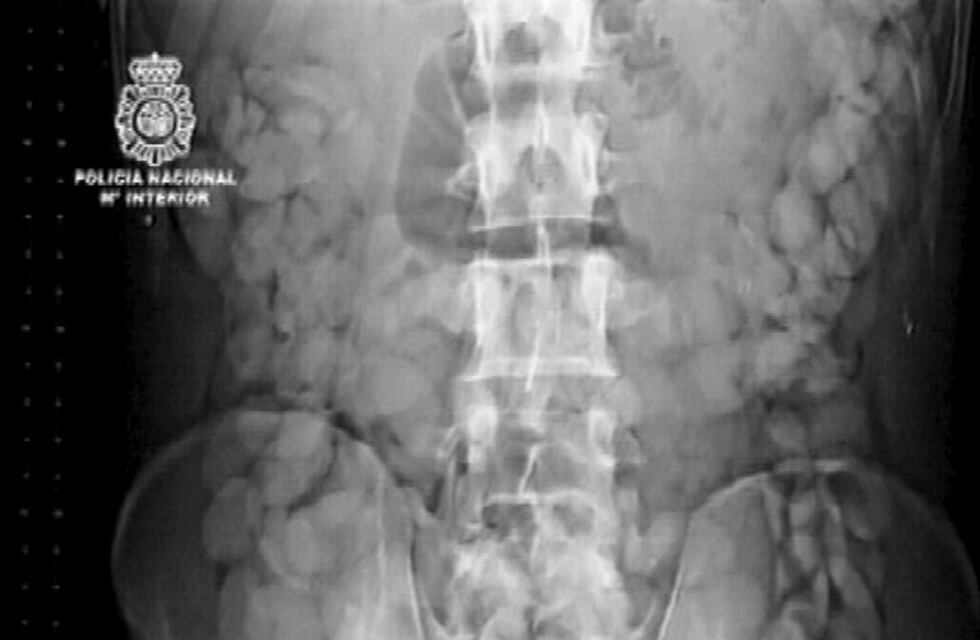

Jonathan Luis Rojas Vera es un ingeniero en refrigeración chileno que se tragó 20 cápsulas de cocaína suficientes para armar casi 5 mil dosis. Bajó en el aeropuerto de Comodoro Rivadavia para intentar vender la droga en la ciudad. Pero no soportó el dolor, la Policía lo descubrió y terminó operado y condenado a cuatro años de prisión por tenencia de estupefacientes para comercializar. Fue un juicio abreviado donde admitió el episodio.

La mañana del 10 de noviembre de 2015, el encargado del Hotel Playa llamó a la Comisaría del barrio Mosconi. Personal de Drogas Peligrosas concurrió a revisar una situación anómala con un pasajero en la habitación 24. Era Vera, único ocupante, en mal estado de salud. Golpearon varias veces hasta que les pidió que entraran. Había sustancia blanca, pastillas laxantes Dulcolax y un kit de enema Enemol. Todo indicaba que era una "mula": se había hospedado la madrugada del domingo, era martes y aún no salía de la habitación.